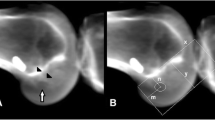

All patients underwent a standardised LDCT 6 weeks post operatively. A Siemens Definition AS+ CT scanner (Siemens Somatom Definition AS+; Siemens Healthcare, Forchheim, Germany) was used. The data was then processed through the clinical software application iterative Metal Artifact Reduction (iMAR) algorithm for metal artifact reduction. Data was imported into Philips 2nd edition software (Philips Medical Systems North America, Shelton, Conn) to create a complete 3D volume reconstruction of each femur (to 10 cm above the femoral condyle) and tibia (to 1 cm below the tibial tubercle). The femoral 3D reconstruction had at least 90% overlap of femoral condyles and then virtual subtraction of the medial femoral condyle at the highest point of the intercondylar notch, leaving the most medial sagittal aspect of lateral femoral condyle with tunnel position on view (Fig. 1). The tibial 3D reconstruction was an axial view, adjusted to view the most superior aspect of the proximal tibia with the femur and patella removed (Fig. 2). The 3D reconstructions were imported into IntelliSpace Patient Archiving and Communication System (IntelliSpace PACS Enterprise; Philips) for measurement.

Femoral tunnel measurement

The quadrant method described by Bernard was used to assess femoral tunnel position (Fig. 1) [11, 16]. Point A is the centre of the femoral tunnel on the medial aspect of the lateral femoral condyle. A rectangular reference frame is superimposed. Distance B is the total sagittal diameter of the condyle, measured along the intercondylar notch roof, limited by the shallowest and deepest contours of the condyle. Distance C is the height of the intercondylar space, measured as the perpendicular distance between the notch roof and a parallel line tangential to the lowest point on the femoral condyle. Distance B and Distance C define the intercondylar space and create the axes for the quadrant system. Distance D is measured between Point A and the deep contour of the condyle, parallel to the notch roof. Distance E is the perpendicular distance between Point A and the notch roof. Femoral tunnel position in the sagittal plane is the defined by calculating ratios D/B and E/C.